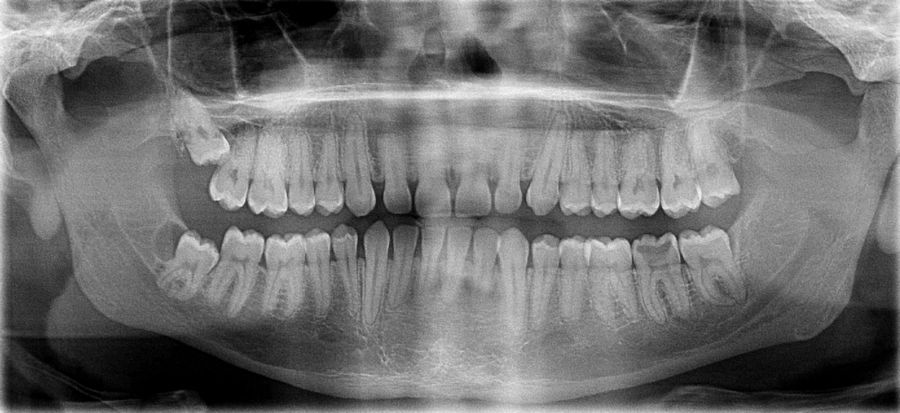

Панорамный снимок челюсти позволяет стоматологу получить изображение сразу всех зубов, включая верхнечелюстные суставы.

На рентгене отображаются зубные каналы, корни, костная ткань, пломбы и импланты.

Что такое ортопантомограмма (ОПТГ) зубных рядов

Ортопантомограмма (ОПТГ) – это рентгеновский снимок всей челюсти. Он помогает обнаружить скрытый кариес под пломбой, искривление зубного ряда и другие заболевания.

Панорамный снимок челюсти является необходимой диагностической процедурой при лечении неправильного прикуса. ОПТГ позволяет выявить неправильное развитие и расположение зубов и челюстей, переломы челюстных костей и корней зубов.

Кроме того, сделать панорамный снимок зубов потребуется при планировании протезирования, перед лечением пародонтита и пародонтоза.

Что видно на панорамном снимке?

- он демонстрирует состояние всех без исключения зубов на нижней и верхней челюсти, а также состояние гайморовых пазух и височно-нижнечелюстного сустава;

- с помощью него доктор может увидеть зачатки постоянных зубов у малышей и обнаружить возможные патологии их развития;

- ортопантомограмма информирует о кариозных очагах, гранулемах и кистах, ретинированных «зубах мудрости»;

- с помощью нее можно определить заболевания пародонта и костной ткани еще на ранних этапах;

- врач получает максимум информации для проведения коррекции, протезирования и дентальной имплантации;

- панорамный снимок позволяет проверить качество проведенного лечения, в частности, пломбирования корневых каналов.